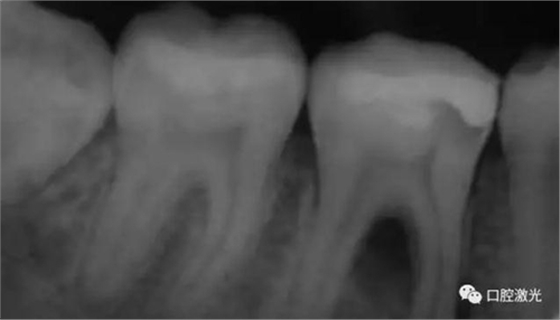

11、21 治療前

對瘺管位置進(jìn)行激光氣化

激光治療后即刻

治療前和2個月后效果對比